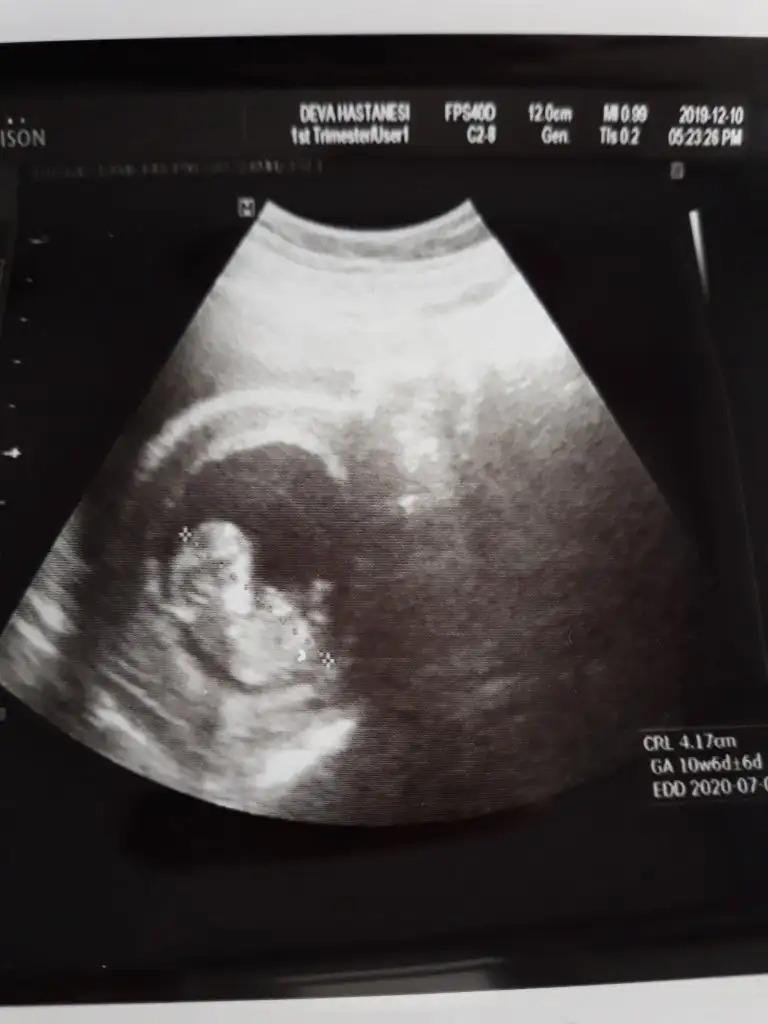

Değişmeyebilir saglıkla gelsinUsg 12 haftalık, doktorun tahmini 16 haftalık![]()

12+1 canım:) doktor da erkek dedi bakalım net değil ama netleşince oy vercemNet olmamakla birlikte erkek diyorum kaç haftalık 11+ yada 12+ olmalı

Net olmamakla birlikte kız gibiOldu heralde kızlar 12+5 66 mm dedi tahmininiz nedir?